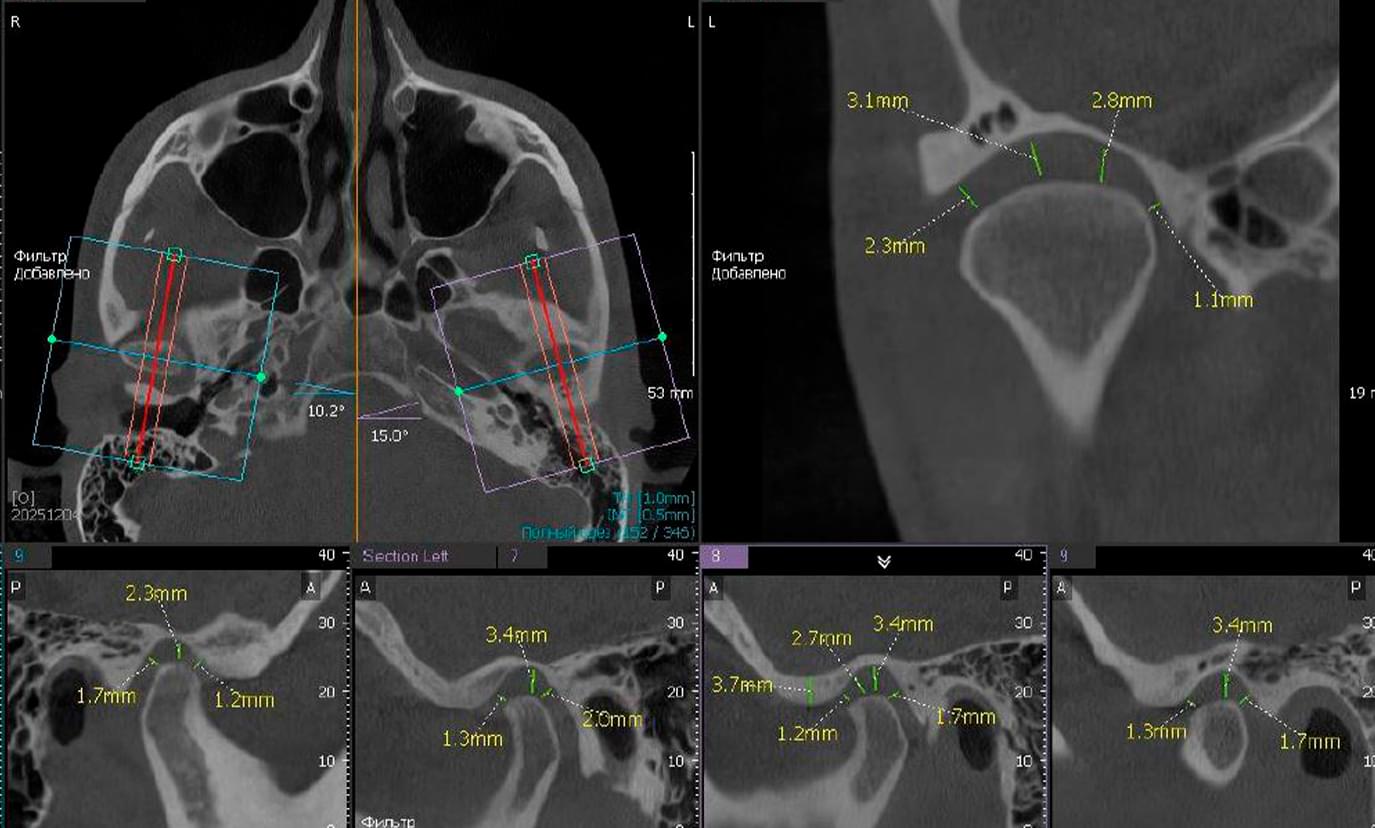

1️⃣ Анатомія та положення суглобів:

● Лікар описує положення голівок суглобів, які наразі розташовані несиметрично та зміщені назад

(дистальне положення) відносно суглобової ямки з обох боків.

● Суглобові ямки мають ознаки деформації з обох сторін.

1️⃣ Стан суглобової щілини (простір всередині суглоба):

● Суглобові щілини різко звужені у задніх (дистальних) та верхньо-бічних (латеральних) відділах

з обох сторін.

● Це свідчить про зміну простору, в якому працює суглобовий диск.

1️⃣ Кісткові зміни та регенерація (ремоделювання):

● Виявлено ознаки ремоделювання (перебудови кістки) суглобових голівок та бугорків з обох боків.

● Наявні ознаки склерозування (ущільнення кістки під хрящем) та формування остеофітів (невеликих

кісткових розростань) на передніх поверхнях голівок.

● З лівого боку візуалізуються деструктивні зміни (порушення цілісності) кортикальної пластинки

суглобової голівки.